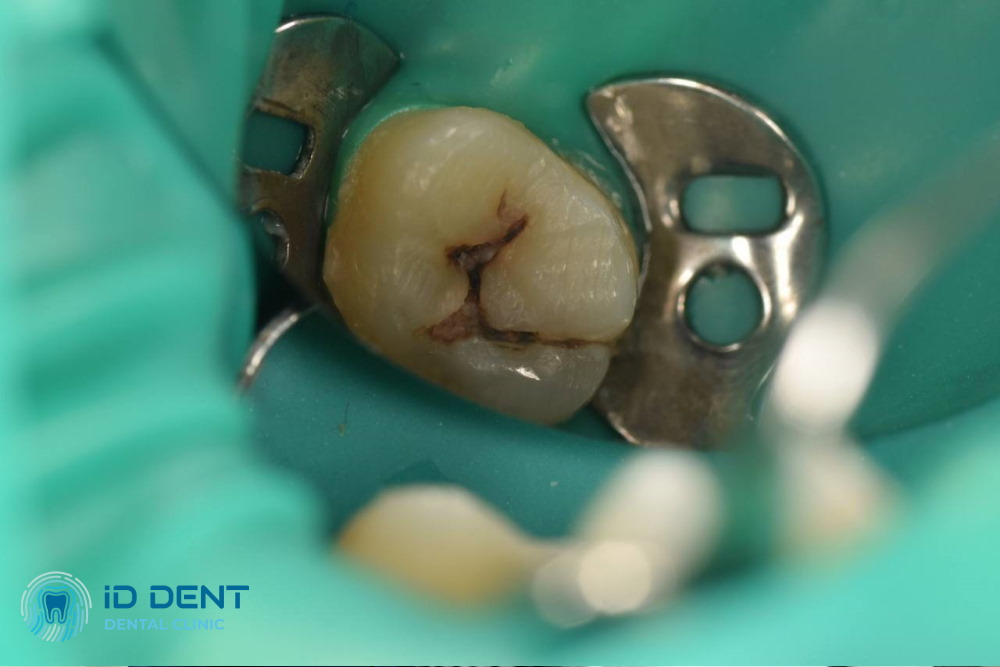

Tratamiento de caries media

Los principales síntomas de la caries media son sensibilidad a temperaturas, dolor, aparición de manchas oscuras en el esmalte. Los dentistas de la clínica ID Dent en Lesnoy Massif le ayudarán a lidiar con este problema. Aplicamos técnicas modernas para el tratamiento de caries y sabemos cómo detener la destrucción del diente en una sola visita y prevenir complicaciones. ¡El precio del tratamiento, la garantía de los servicios y el ambiente confortable en la clínica son ventajas que ofrecemos a cada cliente!

El tratamiento de la caries media se realiza mediante el método clásico, utilizando el torno dental. El odontólogo anestesia la zona necesaria, elimina los tejidos dañados, realiza una limpieza antiséptica del área y coloca un empaste definitivo.